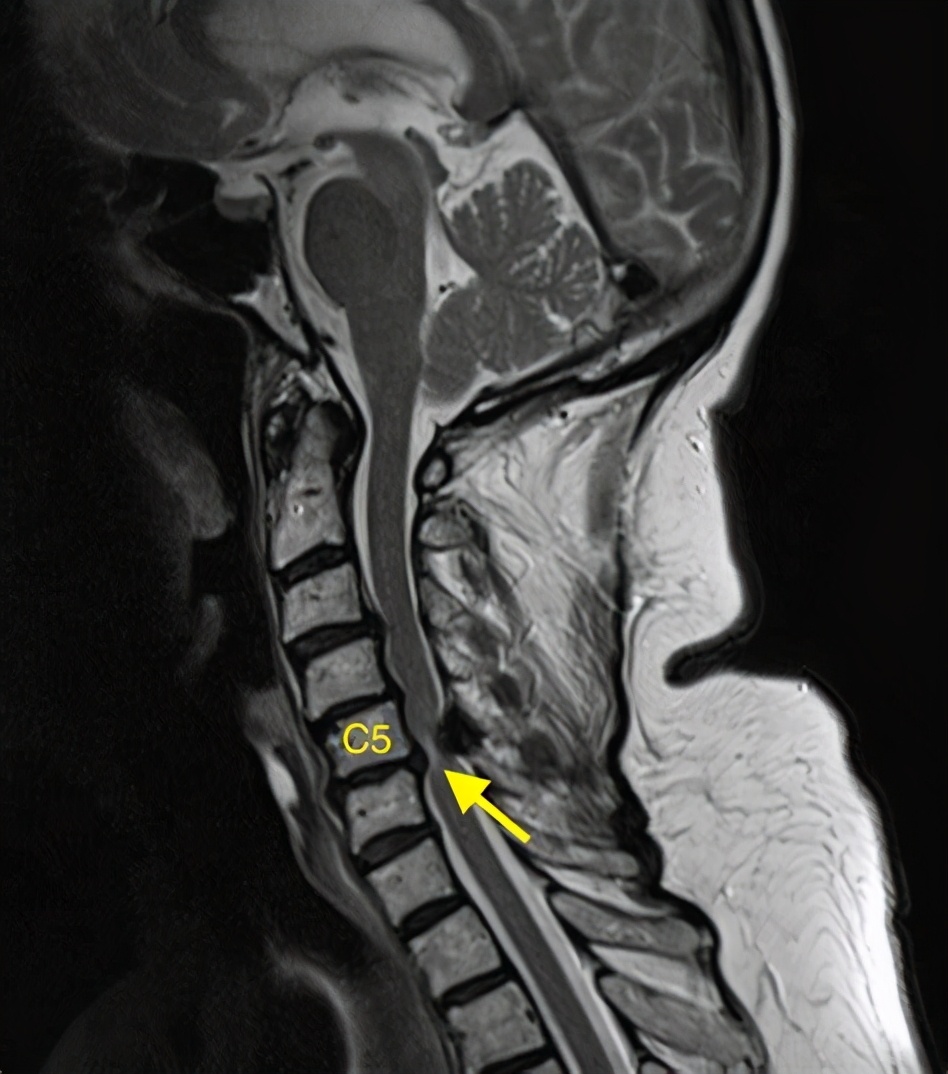

其实颈椎病是有很多类型的,这个患者就是脊髓型颈椎病已经挺严重的了,以前碰到过还跟他说千万不要摔倒,容易瘫痪,没想到冬天天冷路滑真的摔了一跤。

摔跤之后就感觉四肢无力麻木,幸亏送到医院及时做了手术才幸免于瘫痪。

但是最为严重的也是临床中最值得注意的就是脊髓型颈椎病了。

如果脊髓受到压迫,遭受外伤或者其他*力暴**因素之后,就容易出现脊髓损伤,脊髓损伤,大家可能都听过,严重的时候会出现瘫痪。